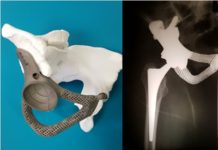

— Звертаючись до ендопротезування, зазвичай зупиняються на вимушених замінах тазостегнового, а також колінного суглобів. Але ж іноді є необхідність і в пересадці ендопротезів для відновлення безповоротно ушкоджених, з тих чи інших причин, плечового і ліктьового суглобів…

— Дійсно, нам вдалося, без ускладнень, пересадити понад 130 плечових і ліктьових ендопротезів. Ось ви тримаєте зразки в руках і відчуваєте, що це результат високих технологій, включаючи і матеріали. Ендопротези імпортні, вони — результат величезного пошуку, і це, відверто кажучи, поки доцільніше, ніж винаходити «велосипед» з відчутним ризиком невдач.